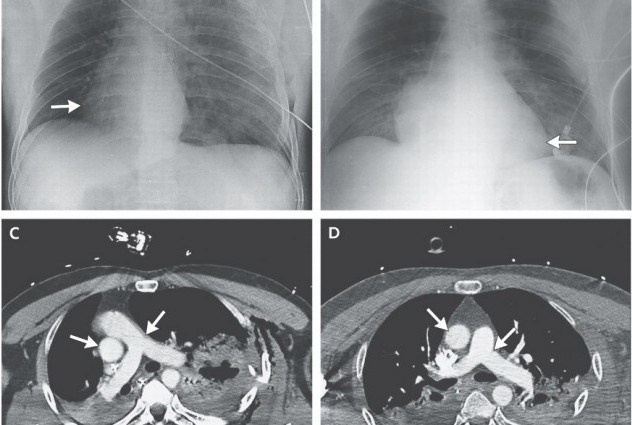

| Ảnh X quang và chụp cắt lớp phần lồng ngực của người đàn ông Italy cho thấy trái tim của ông xoay 90 độ sang bên phải. Ảnh: IFL Science |

Tên y học của tình trạng này là tật tim sang phải, một di chứng của dị tật thai nhi. Tuy nhiên, trước khi tai nạn xảy ra, tim của người đàn ông vẫn nằm bên trái. Do phổi của ông thủng trong tai nạn, không khí tràn ra ngoài, đẩy tim sang phía bên phải lồng ngực cùng động mạch phổi phải, động mạch chủ và hệ thống bơm máu. Huyết áp của ông tụt xuống mức nguy hiểm. Khi bác sĩ rút hết không khí trong phổi bệnh nhân, hệ thống cơ và hệ thống bơm máu liền chuyển dịch về vị trí cũ. Huyết áp bệnh nhân lại tăng về mức bình thường. Điều đáng ngạc nhiên nhất là người đàn ông hoàn toàn tỉnh táo sau tai nạn.